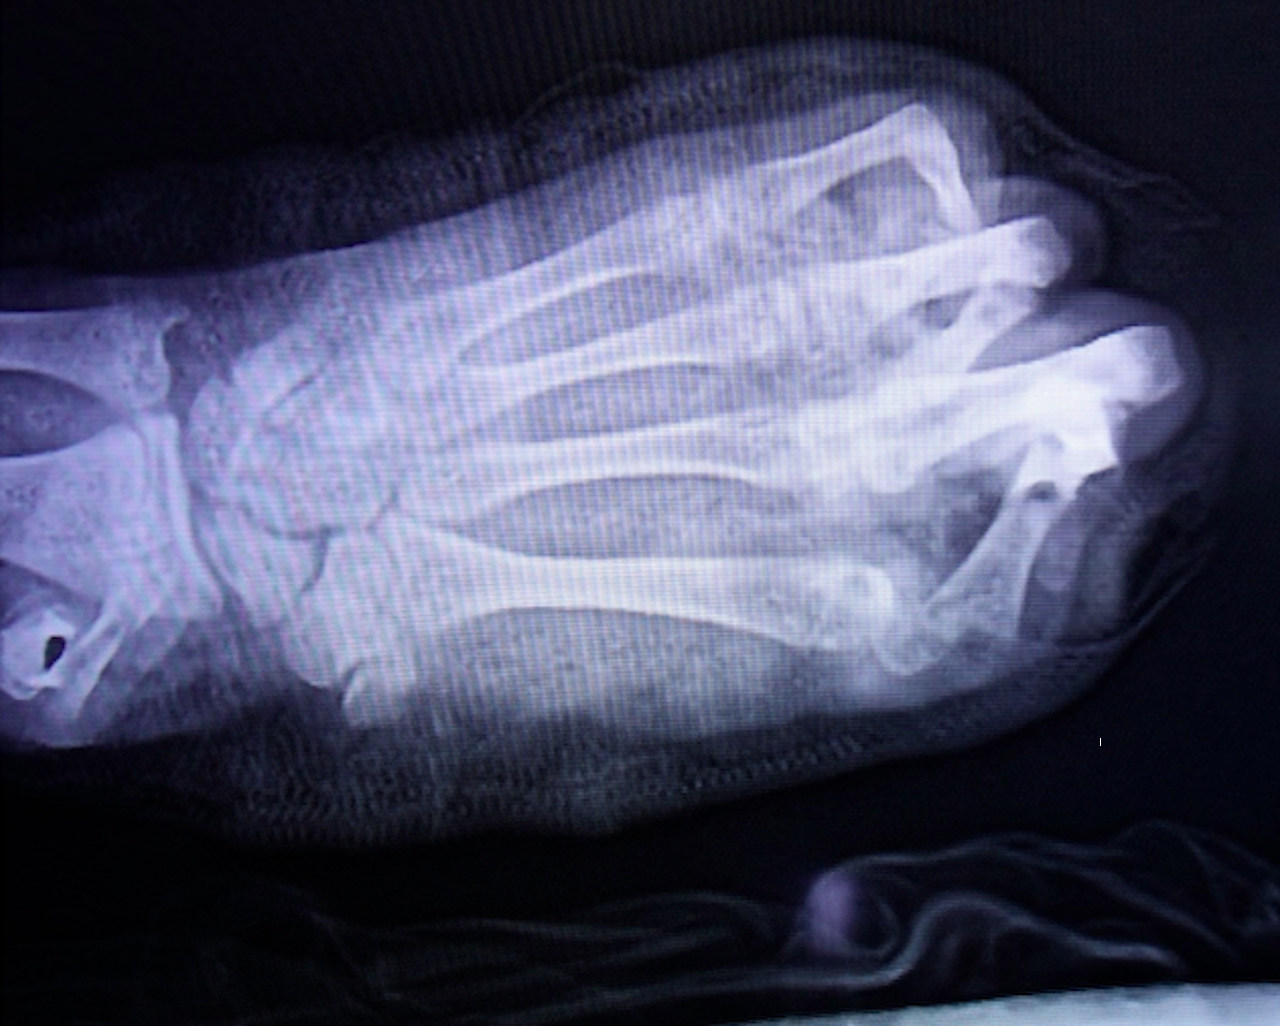

Hình ảnh chụp phim bàn tay dập nát của thiếu niên. Ảnh: BVCC

Theo các bác sĩ, bàn tay trái của bệnh nhân bị dập nát gần như hoàn toàn, kèm theo vết thương phần mềm vùng đùi trái. TS.BS Nguyễn Quang Vịnh – Khoa Phẫu thuật Chi trên và Vi phẫu cho biết, đây là một trong những trường hợp tổn thương nặng nề, điển hình do pháo nổ gây ra.

Dù được cấp cứu và phẫu thuật khẩn trương, sau nhiều nỗ lực, ê-kíp điều trị chỉ có thể giữ lại 2 trong số 5 ngón tay cho người bệnh. Toàn bộ vùng gan tay và cổ tay bị dập nát nặng, khiến quá trình điều trị dự kiến kéo dài với nhiều cuộc phẫu thuật tiếp theo. Tiên lượng lâu dài, bệnh nhân có thể chỉ phục hồi được một phần chức năng rất hạn chế của bàn tay trái.